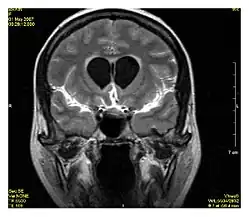

| Double inversion recovery | DIR | Simultaneous suppression of cerebrospinal fluid and white matter by two inversion times.[16] | High signal of multiple sclerosis plaques (pictured).[16] |

| |